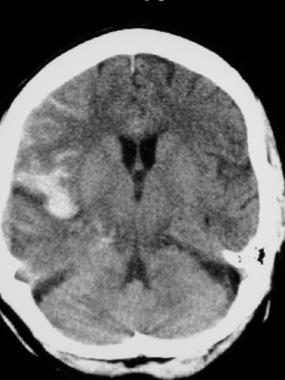

-Always start with non-contrast HEAD CT

-Picks up 92 % of SAH if <24 hours but sensitivity is highest in first 6-12 hours after SAH (~nearly 100 %!) but drops to about 60 % by 5d.

- SAH on CT scan